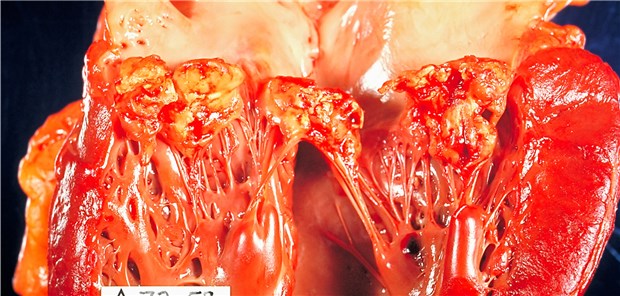

Infektiöse Endokarditis: Meist sind Staphylokokken am Werk.

© Science Faction / Centers for Di

Kardiologie

Infektiöse Endokarditis betrifft meist natürliche Klappen